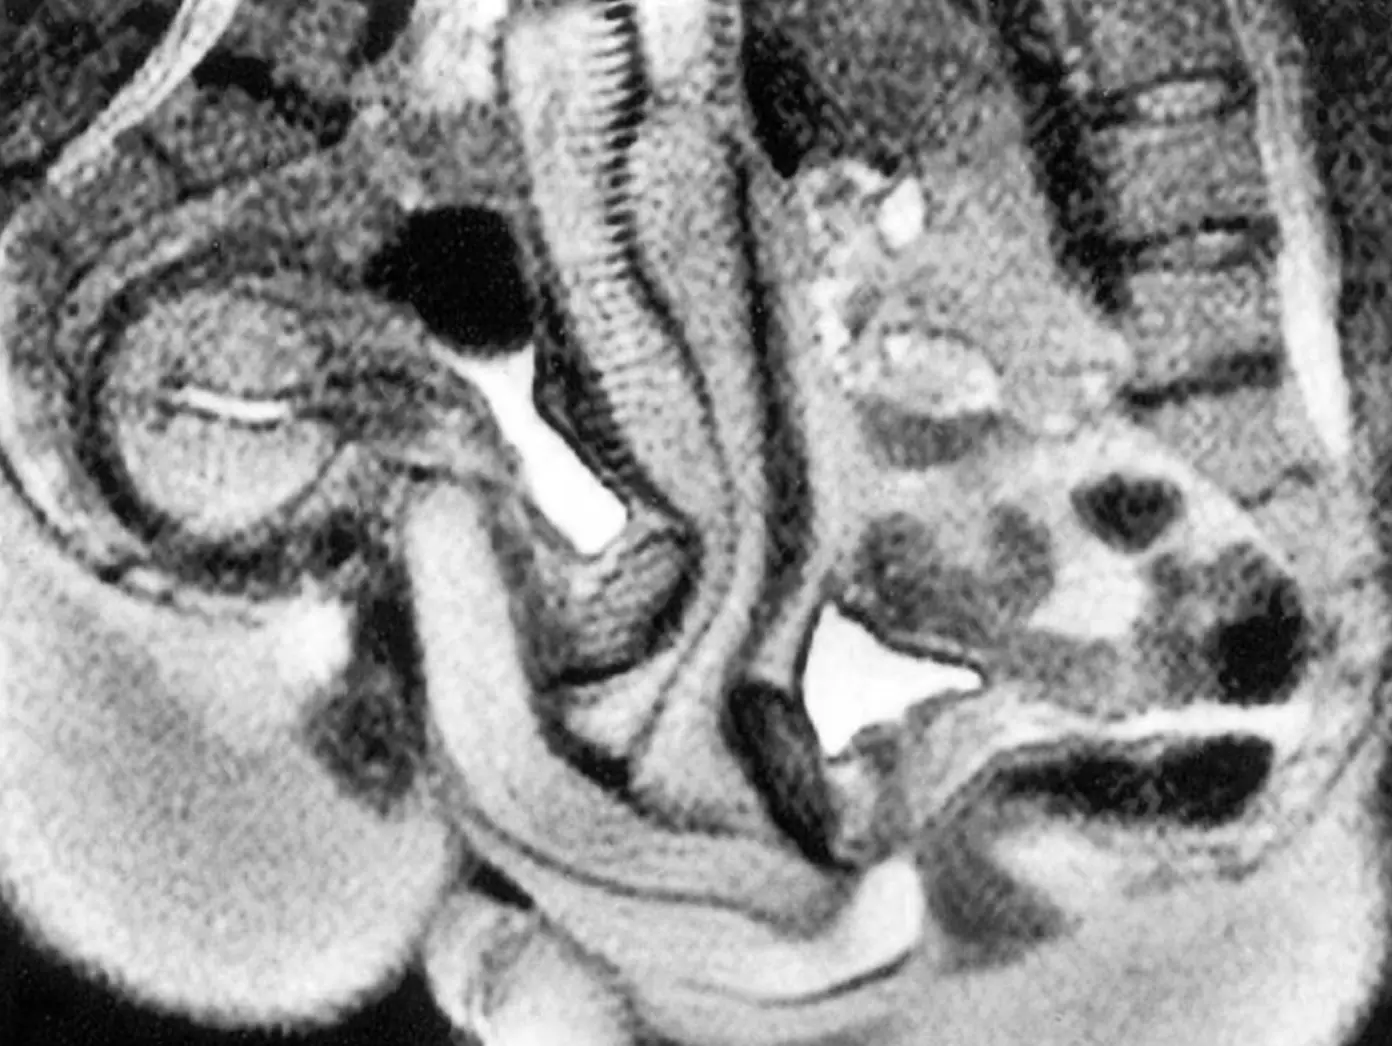

Instead, the couple opted for the spooning position, and before you dismiss it as a silly science experiment, the images that were later created actually helped to change a lot of people's minds about what happens to the body during sex.

Their images became the centre of a hugely popular British Medical Journal entry in 1999, which is still read by thousands of people every month, as people who think science is sexy are no doubt forced to get creative in the wake of the UK's new porn crackdown.

Although many men and women might struggle to perform in front of someone else, let alone several scientists while literally inside a very small machine, the images created by Ida and Jupp showed those in the medical industry that the vaginal canal was, in fact, curved.

The couple, who are still together to this day, were more focused on how cute they 'fit together', but a lot of credit must go to both for teaching the world more about the body, as it revealed that the man's penis bends to fit the shape of the woman's vaginal canal.

This was in direct contrast to a painting from Leonardo da Vinci, which had left people believing that the vagina was a straight cylinder for more than 500 years.